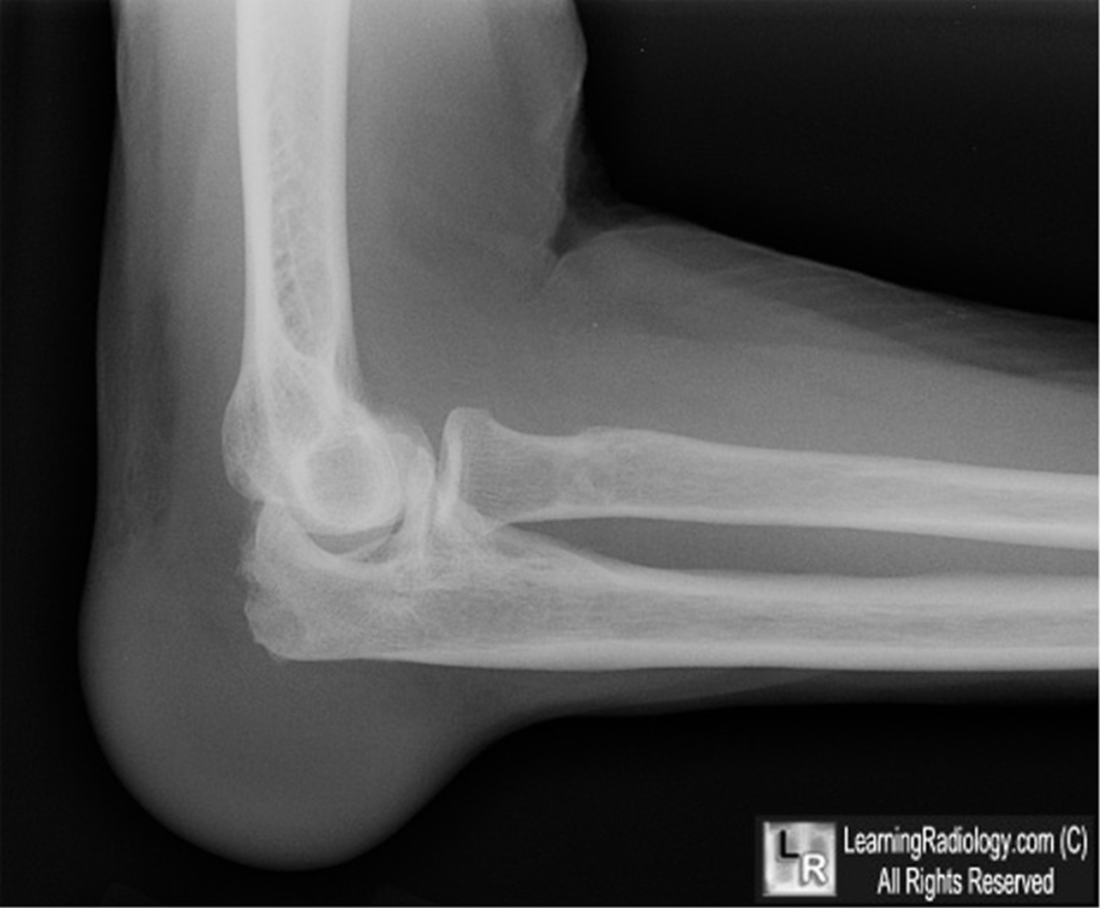

This patient with history of drinking moonshine presents with elbow pain.

What is gout? Olecranon bursitis with erosions.